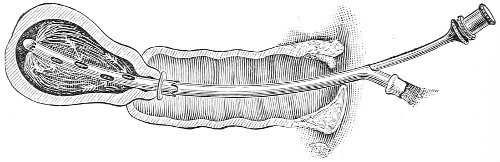

Examination of External Genitals and Pelvic Structures.—To examine the external organs of generation and the pelvic viscera the woman should be placed upon a table. In some cases the physician may be obliged, for want of proper facilities or on account of the physical condition of the patient, to make his examination upon a bed. Such an examination, however, is never so satisfactory or so thorough as the examination made with the woman upon the examining-table. A great number of gynecological tables have been introduced. The one which seems to the writer the best, on account of its simplicity and the perfect relaxation of the abdominal muscles furnished by it, is shown in the accompanying illustration (Fig. 1). It is a plain wooden table, at the foot of which are attached the upright supports for holding the stirrups for the feet, such as have been devised by Dr. Edebohls. By this arrangement the feet and legs are supported without any effort on the part of the woman; when the buttocks are drawn well down to the foot of the table there is a certain amount of flexion 23 of the pelvis upon the trunk, and the most complete attainable relaxation of the abdominal muscles is secured.

Fig. 1.—Woman in the dorsal position with feet supported in Edebohls’ stirrups.